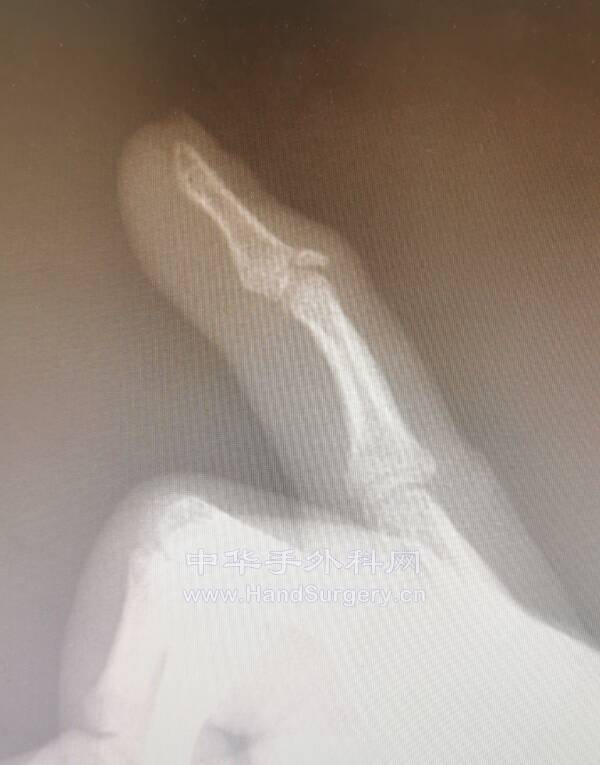

陈旧性骨性锤状指

外伤后半年

咨询过多位手外科专家

都说不用做